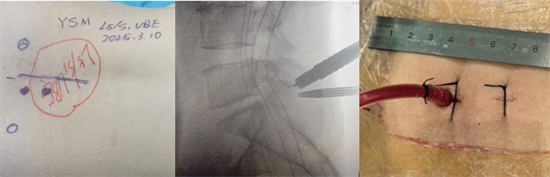

術前影像資料顯示L5/S1巨大脫出椎間盤并向近端高度游離

患者陽某某,女,50歲,因反復腰部疼痛7年加重,并右下肢疼痛麻木半月到衡南縣人民醫(yī)院就診。骨科二區(qū)主任陳軾接診了患者,門診MRI檢查發(fā)現(xiàn)陽女士為典型L5/S1巨大椎間盤脫出并壓迫神經(jīng)根,保守治療無效,建議手術治療。苗驚雷教授與縣醫(yī)院骨科二區(qū)專家團隊為陽女士量身定制了無需內(nèi)固定、創(chuàng)傷更小的UBE微創(chuàng)手術方案。術中通過兩個7mm的切口,精準摘除脫出髓核,徹底解除神經(jīng)壓迫。術后次日,陽女士下肢癥狀顯著緩解,已可自主下床活動。

術中圖片顯示,切口7mm,僅需縫合1針